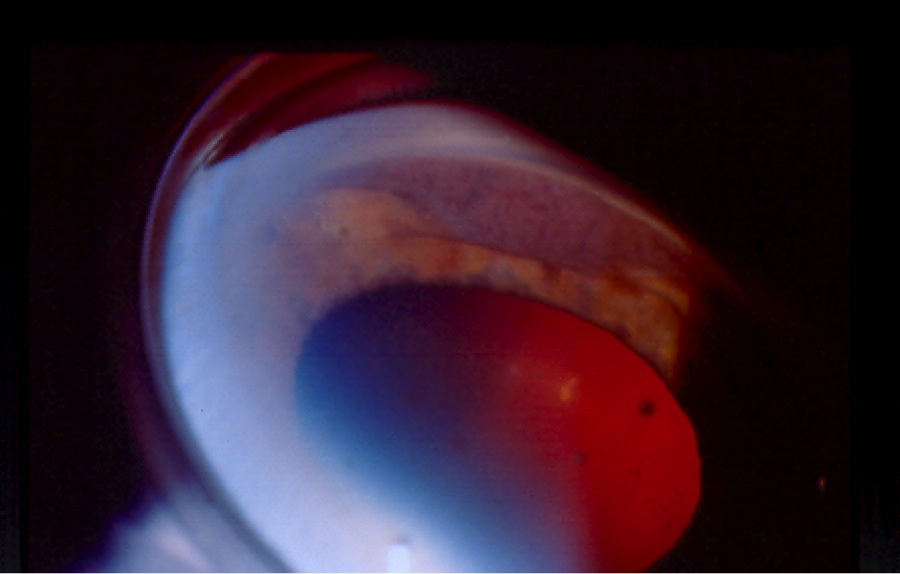

Figures 1(a) & (b). Gonioscopic views of cyclodialysis clefts after paintball injuries to two different eyes

On gonioscopy, a cyclodialysis cleft is visible as an abnormal region posterior to the scleral spur displacing the iris root and ciliary body posteriorly. The appearance of the cleft region can vary considerably, and can look white (like sclera), black, or gray (Figure 1(a) & (b)). Clinical evaluation by gonioscopy is often difficult in a soft eye with a shallow or flat anterior chamber, and can be further impaired by corneal folds/edema or hyphema after trauma. Injection of viscoelastic into the anterior chamber, with or without application of topical pilocarpine to maximally open the angle, can improve the view. Sometimes, a cleft may be hidden adjacent to broad-based peripheral anterior synechia; such areas should be carefully inspected during gonioscopy. In many cases, complementary use of imaging (see section 2.3 Imaging, below) is necessary to confirm the diagnosis and gauge the size of the cleft.[1]